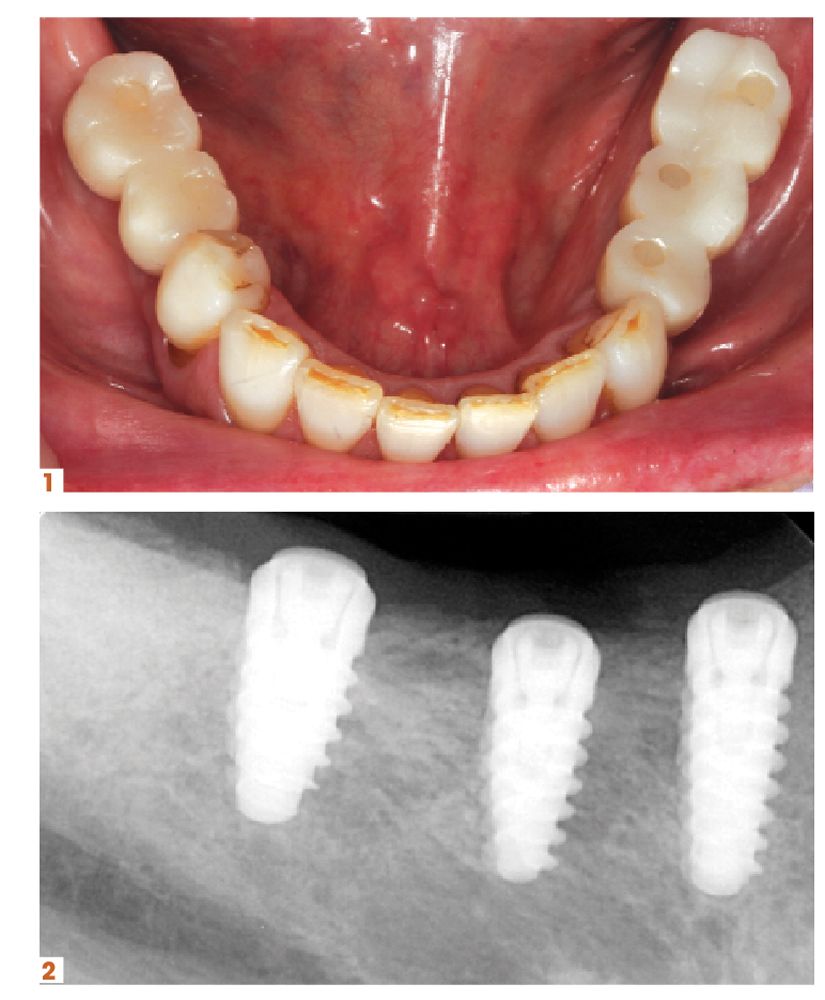

Another area of growth for practices can come from providing more implant services.

“Twenty-two years into my career, I didn’t realize how big of a game changer implant placement would be for my practice. Now that we can tell patients that we can handle it here in the practice, most patients are eager to move forward with treatment,” says John R. Nosti, DMD. “It’s, ‘Oh, you can do this now? That’s great!’

“So being able to offer that service to my patients, who trust me and know that I’m capable of providing them the care or I wouldn’t offer it to them, has been great for them as well as my practice. It’s convinced a lot of patients who’ve been on the fence, even though they wanted the implant, into accepting treatment. And then there’s new patients I’m meeting who have been to my website or seen the marketing pieces we’ve put out. They’ve seen the smiles we create and the testimonials, and they come to the practice because it’s all done in my office.”

There are a few products, and courses, in particular that Dr Nosti counts on to help with his growth.

“I strongly recommend that anyone who’s interested in placing implants take the Misch-Resnik Implant Institute continuum. Just in the first session alone, you learn enough about extracting and grafting to bring that back to your practice and add it to the services you offer,” he says. “Being able to perform predictable bone grafting procedures for your patients can add enough revenue to your practice to pay for the entire continuum. And that’s before implant placement even enters the picture.”

He adds, “Doctors really owe it to themselves to look into implants and have that be a part of their practice. Their patients will be able to chew food easier, smile with more confidence, and enjoy all of the life improvements that implants bring. And that’s amazing because, don’t we all want to better our patients’ lives?”

Figures 1-4.For his first implant surgery, which was completed at the time he was attending courses at the Misch-Resnik Implant Institute continuum, John Nosti , DMD, placed 5 Hahn™ Tapered Implants in the posterior mandible for a patient who was especially eager to have him complete the entire process, from implant placement to the final screw-retained restorations. Glidewell offers a complete solution for implant and restorative cases. This solution is designed to provide the best care for patients and the greatest efficiency in terms of clinical workflows. The company’s new lifetime warranty stands as a commitment to the quality of the company’s implants and restorations and reflects the solid research and development and clinical validation dedicated to earning the trust of the dentists that Glidewell serves.